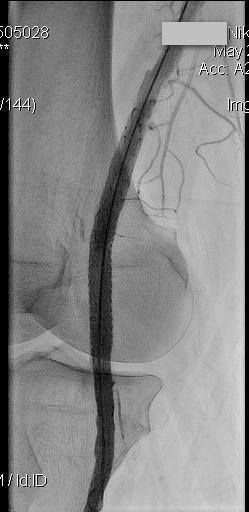

16 июня 2016 года в ЦЭЛТ, в отделении сердечно-сосудистой хирургии, состоится семинар и вебинар по самым актуальным вопросам интервенционной кардиологии и ангиологии на тему: «Современные подходы лечения пациентов со сложными поражениями артерий нижних конечностей».

В программе мероприятия: демонстрация эндоваскулярных операций в прямом эфире, лекционная часть и обсуждения докладов.